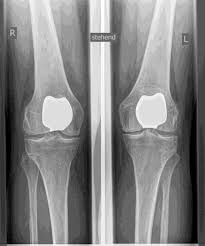

PATENT KNEECAP JOINT REPLACEMENT (PFJ)

Disturbances in mobility or instability as well as the shape of the kneecap (dysplasia) can lead to cartilage damage and arthrosis ISOLATED IN THE patellofemoral joint. IF THE OTHER COMPARTMENTS ARE FREE OF ARTHRITIS, an isolated partial joint replacement of the kneecap-posterior surface joint is possible.